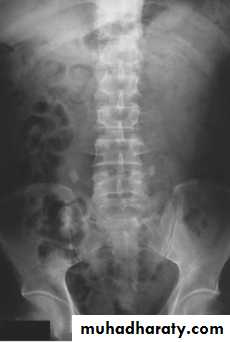

The IVU series consist of:1-KUB film…To identify any calcification like stones or nephrocalcinosis.

2-Post contrast film…

• Check that the kidneys are in their normal positions (the left is usually higher than the right)

• Identify renal outlines…For any bulge or indentation.

• Measure the renal length (10-16 cm) these are higher than those for renal size on ultrasound.

• Calyces should be evenly distributed and symmetrical.

• Its shape is normally cupped , when dilated becomes clubbed.

• The normal renal pelvis is funnel shaped

• The ureters are usually seen in only part of their length on any one film of an IVU.

• The bladder is centrally located and should be smooth in outlines.